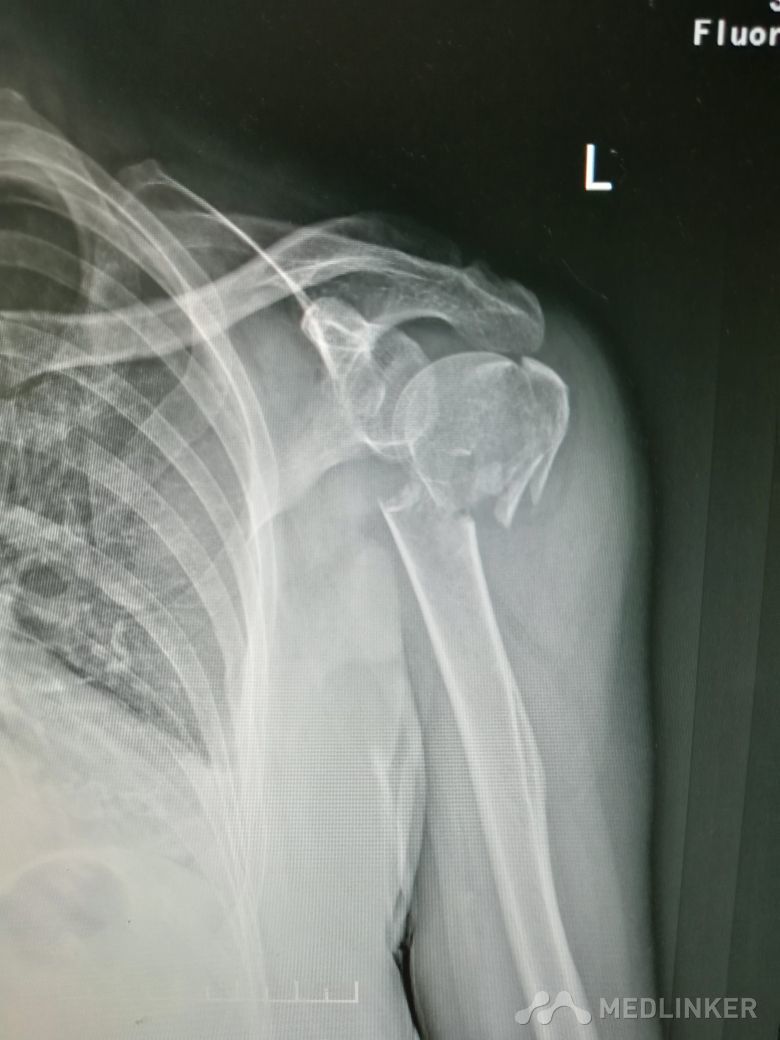

肱骨近端骨折 Neer IV型

患者,女性,55岁,因外伤致左肩疼痛六小时入院,既往无其他慢性病史

查体 右肩肿胀,畸形,活动受限,压痛,皮下淤血,右桡动脉搏动存在

完善相关检查,在腰麻下行右肱骨近端骨折切开复位内固定术

肱骨近端骨折占到肱骨骨折的45%,肱骨近端锁定钢板具有低切迹、高弹性、生物力学性能优良等特点,可以起到角度稳定控制旋转的作用。但是对于严重粉碎性肱骨近端骨折而言,单纯的肱骨近端锁定钢板不一定能够提供稳定的固定,手术之后仍有可能出现内翻塌陷、前后成角、螺钉切出、骨折畸形愈合、骨折不愈合等并发症。